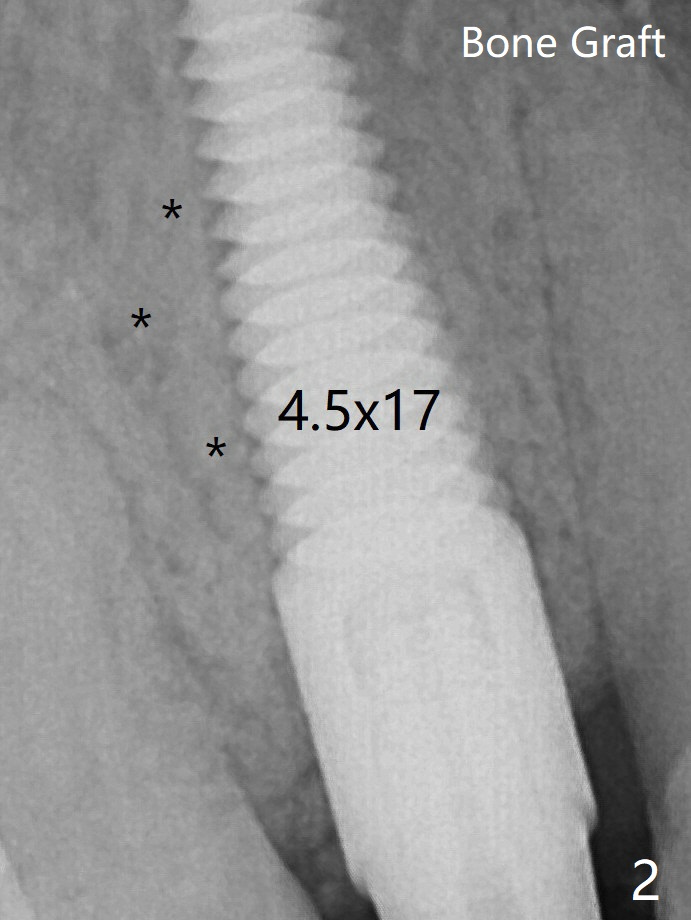

Before placement of a 4.5x17 mm tissue-level implant (Fig.2, (*: bone graft, as compared to preop bone defect (*))) and after osteotomy for bone-level one, PRF and mixture of autogenous bone and allograft are pushed from the socket through the buccal defect for repair (Fig.3 arrowheads).